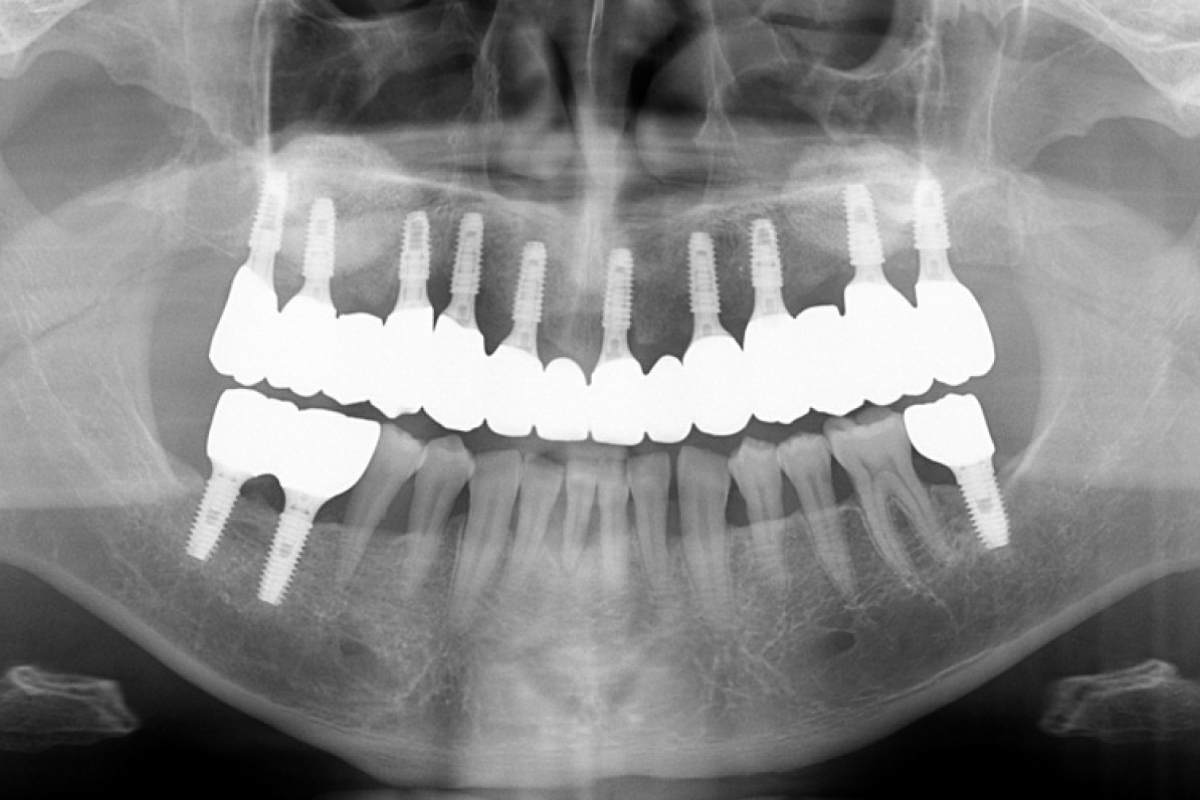

임플란트 치료 후 X-ray

BEFORE AFTER

실제 진료에서는 환자 개개인의 골 상태, 잇몸 상태, 전신질환 여부를 종합적으로 평가하여 임플란트 전·후를 예측하고 계획한 뒤 치료를 진행합니다.